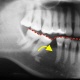

Mit den Zähnen ist es so ähnlich wie mit den Gliedern in einer Kette. Jeder Zahn ist von seiner Architektur her perfekt auf seine jeweilige Aufgabe aufgebaut. Doch das System funktioniert nur so gut wie das sprichwörtlich schwächste Glied in der Kette. Der Verlust nur eines einzelnen Zahnes bedingt, dass eine unterbrochene Zahnreihe entsteht und das Zusammenarbeiten der Zähne gestört ist. In aller Regel entsteht ein so genanntes instabiles System. Das bedeutet, dass der Zahnverlust zwangsläufig zu negativen Veränderungen führt.

Zahnlücken sind nicht nur äshtetisch negativ

...sondern haben zahlreiche ungünstige Auswirkungen.